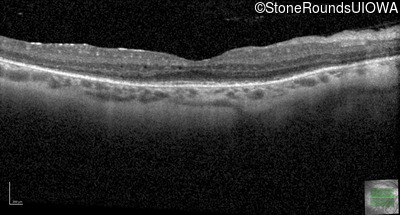

Optical Coherence Tomography - Right - 20/50 +1

Exemplar / OCT Stack

Optical Coherence Tomography - Left - 20/50 +1